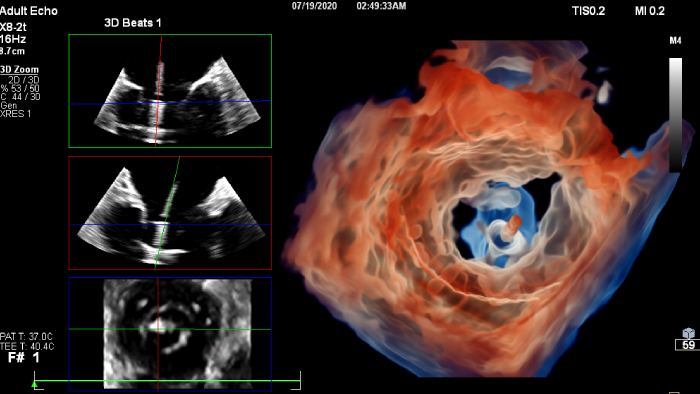

If you were registered for ESC 2023, but were not able to attend the satellite symposium, you can still view it through the ESC website. Top cardiology thought leaders addressed some of the major challenges in peri-interventional and diagnostic echocardiography, such as advancing and complementing imaging techniques during tricuspid valve interventions, a revolutionary imaging workflow for occlusion of the left atrial appendage, and the importance of first-time-right ultrasound imaging during cancer therapy.

You can still access recordings of 4 full days of hands-on workshops about best practices in multimodality cardiac imaging with expert teams. See first-time-right imaging for cardiac care, including valvular and related diseases, cardiomyopathies, and intracardiac masses and cardiac tumors. Sign up to receive access to these on demand sessions and other news about Philips and cardiac care.